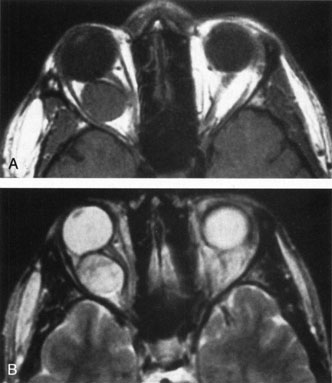

Contrast-enhanced CT of the orbits with direct and coronal cuts is the radiologic study of choice for these patients.45 A well-demarcated, encapsulated oval or rounded mass is revealed, which is typically intraconal in the lateral part of the middle third of the orbit (Fig. 5) but occasionally may extend to the extraconal space.42 Septa within the tumor may be apparent on high-resolution CT. The posterior pole of the globe frequently is indented by the rounded anterior margin of the tumor.42 The optic nerve typically is displaced rather than surrounded by the tumor. Subtle outward bowing of the lateral orbital wall or increase in orbital size may be present, consistent with a long-standing, slowly growing mass lesion.10,42 Enhancement with intravenous contrast occurs and may be homogeneous or inhomogeneous.10,45 Rarely, cavernous hemangiomas may occur as an intraosseous tumor within the orbital or facial bones.42,53–55 Although usually an isolated intraorbital lesion, multiple lesions in one orbit occurred in 8 of 164 (5%) patients of three combined large studies,10,42,45 and bilateral multiple cavernous hemangiomas also have been described.56 In contrast to patients with venous flow malformations in which phleboliths are common, phleboliths are rare in cavernous hemangiomas. Three large studies comprising 164 patients with cavernous hemangioma all reported that no calcification was detected within the tumor.10,42,45If the diagnosis is still unclear or if better definition of details and localization of the lesion is required, then MRI should be performed. Magnetic resonance imaging demonstrates nonspecific characteristics of a lesion isointense to muscle and gray matter on T1-weighted images and hyperintense on T2-weighted images (Fig. 6).57 The lesions show initial central patchy enhancement, which fills up homogeneously within 20 to 60 minutes.58 If ultrasonography is performed, B-scan ultrasonography shows a well-circumscribed mass with a sharply defined anterior acoustic border.23 A-scan ultrasonography shows high reflectivity of the echo signals resulting from the multiple blood-filled vascular channels, regular internal structure with a higher anterior and posterior spike marking the capsule, and moderate sound attenuation (angle of decrease of the echo spike within the lesion).24 Arteriography is not indicated.

Fig. 6. Cavernous hemangioma. Axial magnetic resonance imaging demonstrates a well-defined, homogeneous intraconal mass that is isointense to muscle and gray matter on T1-weighted image (A), and hyperintense on T2-weighted image (B). Note the displacement of the optic nerve and indented posterior globe.